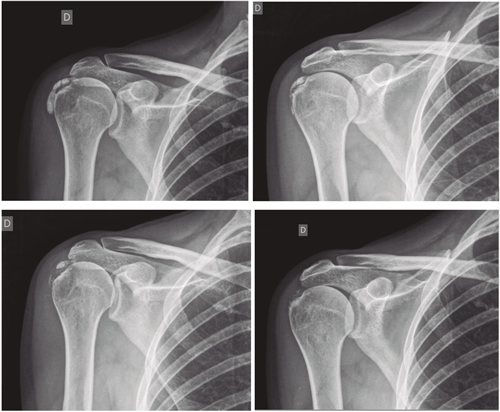

Resultados: Edad media: 54,6 años (n = 138); mujer (73,1 %; n = 101); proporción mujer/hombre 3: 1; tendón supraespinoso (94,6 %; n = 124); subescapular (5,4 %; n = 14); hombro izquierdo (55,1 %; n = 76), hombro derecho (44,9 %; n = 62); bilateral 1,4 % (n = 2); diestros 96,3 % (n = 133); antecedentes personales: tabaquismo (19,5 %; n = 27), diabetes (7,2 %; n = 10). El tiempo de enfermedad promedio fue de 6,08 meses. Dolor agudo-subagudo (menos de 3 meses) 47,1 %; (n = 65), dolor crónico (más de 3 meses) 52,9 % (n = 73). Tipo radiológico: formativo 75,3 % (n = 104), resortivo 24,7 % (n = 34). Número promedio de sesiones: 20. Complicaciones del tratamiento 2,8 % (n = 4): intolerancia/eritema/quemadura. Ocupación: administrativo 39,8 % (n = 55), trabajos manuales 60,2 % (n = 83). El dolor inicial EVA de 7,3 puntos disminuyó significativamente (p = 0,0000) después del tratamiento a 2,7. El tamaño promedio inicial de las calcificaciones fue de 10,7 mm y disminuyó significativamente (p = 0,0000) después del tratamiento a 3,8 mm. Cambio de calcificación: tasa de éxito/curación 55,7 % (n = 77), tasa de mejora 20,2 % (n = 28); tasa de fracaso del 23,9 % (n = 33). La limitación funcional disminuyó de un 10,8 % a un 2,1 %.

Results: Mean age 54.6 years (n = 138). Female (73.1 %; n = 101); female to male ratio 3:1. Supraspinatus tendon (94.6 %; n = 124), subscapularis (5.4 %; n=14); left shoulder (55.1 %; n = 76), right shoulder (44.9 %; n = 62). Bilateral 1.4 % (n = 2). Right handed 96.3 % (n = 133); Personal history: smoking (19.5 %; n = 27), diabetes (7.2 %; n = 10); disease time averaged 6.08 months; acute-subacute pain (less than 3 months) 47.1; (n = 65), chronic pain (greater than 3 months) 52.9 % (n = 73). Radiological type: formative 75.3 % (n = 104); resorptive 24.7 % (n = 34). Average number of sessions: 20.5. Treatment complications 2.8 % (n = 4): intolerance/erythema/burn. Occupation: administrative 39.8 % (n = 55), manual jobs 60.2 % (n = 83).

Average initial pain 7.3 points (VAS scale), significantly decreased (p = 0.0000) post treatment to 2.7. Initial average size of calcifications 10.7 mm and significantly decreased (p = 0.0000) post treatment to 3.8 mm. Change of calcification: success/cure rate 55.7 % (n = 77), improvement rate 20.2 % (n = 28); failure rate 23.9 % (n = 33). Functional limitation decreased from 10.8 % of patients to 2.1 %.